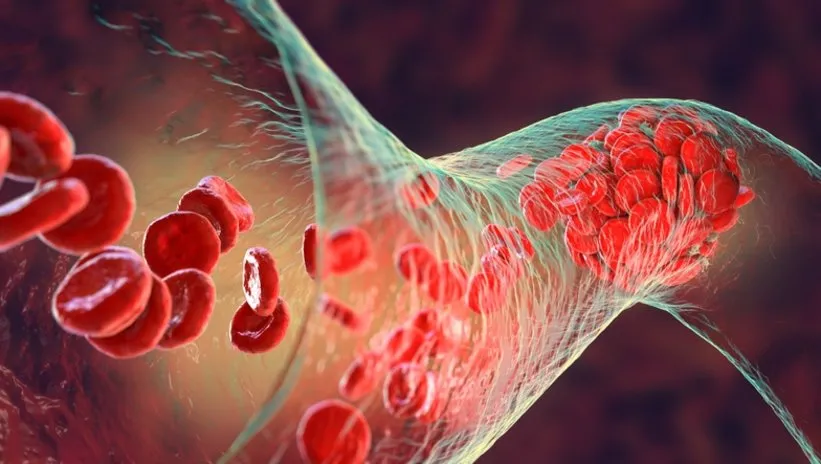

Türkiye'de 2013 yılında İstanbul'da yapılan kongreden 10 yıl sonra ASVS üyelerinin yeniden Antalya'da bir araya geldiği kongrenin tanıtım toplantısı yapıldı. Toplantıda konuşan ASVS Kongre Kongre Başkanı Prof. Dr. Hakkı Tankut Akay, damar hastalıklarının, dünyada bulaşıcı hastalıklardan sonra en fazla ölüm sebeplerinden olduğunu anlattı. Damar hastalıklarının atardamar, toplardamar, lenf hastalıkları olmak üzere gruplara ayrıldığına değinen Prof. Dr. Akay, "Atardamar hastalıkları anevrizmalar ya da damar darlıkları olarak karşımıza çıkarken, ven hastalıkları da toplardamar yetmezliği, varisler ve pıhtı ile birlikte giden ven hastalıkları olarak karşımıza çıkıyor. Bunun dışında lenf hastalıkları da damar hastalıklarının parçalarıdır. Dünyada 2019 yılında 20 milyona yakın insan damar hastalıklarından hayatını kaybetti. Bu periferik arter dediğimiz hastalıklar ya da pıhtıya bağlı hastalıklar olarak karşımıza çıkabilir. Kanser, trafik kazası gibi ölüm sebepleriyle bulaşıcı hastalıklardan sonra en sık hayat kaybettiğimiz sebeplerden biri. Sadece hayatı kaybetme anlamında değil, aynı zamanda maddi kayıplar, iş gücü, uzuv kayıpları ve hayati organlar denilen bağırsak, karaciğer, akciğer damarlarımıza atılacak pıhtıların bu organların beslenme bozukluğu oluşturmasına bağlı çok önemli, hayatı kısıtlayıcı hastalık grubundan bahsediyoruz" diye konuştu.

Fleboloji Derneği Başkanı Prof.Dr. Adnan Taner Kurdal, toplar damar sistemi hastalıklarının toplumda sık görüldüğünü dile getirdi. Tedavisinin diğer hastalıklara göre daha kolay olduğunu anlatan Prof. Dr. Kurdal, özellikle pıhtıya dayalı toplar damar hastalıklarının ciddi ölümle sonuçlanan komplikasyona yol açtığını söyledi. Prof. Dr. Kurdal, gebeliğin damarlarda pıhtı oluşumunu artıran bir durum olduğuna dikkati çekti. Gebe kadınların gebe olmayanlara göre ileri derecede toplar damar pırtısı riskine sahip olduğunu aktaran Prof. Dr. Kurdal, "Gebe kalmayan kadın tüp bebek tedavisiyle gebe kalmaya çalıştığında bu tedaviler pıhtı oluşumuna neden oluyor. Normal şartlarda gebe kadınların hayatını kaybetmesi için risk faktörü, kanama, gebeliğe bağlı yüksek tansiyon ve pıhtı olarak belirlenir. Kanama ve yüksek tansiyon ölümleri azalırken gebelikteki pıhtıya bağlı ölümler birinci sıraya yaklaşmakta. Gebeler taşıdıkları çocuklara can verirken kendi canlarını korumalı. Gebelerin toplar damar pıhtısına yatkın olmasından özel olarak korunmaları gerekir. Tüp bebek tedavisi geniş kapsamlı farklı bir konu. Bazı hanımlarda tüp bebek sahibi olmak için özel hormonal tedavi uygulanıyor. Bu durumda dışardan insanın ürettiği hormonu veriyoruz. Dışarıdan hormon verdiğimiz durumda risk yükseliyor. Doğum kontrol hapının kullanımı da pıhtı riskini artırıyor. Gebe kalmak için ya da gebe kalmamak için dışarıdan alınan herhangi bir hormon düzenleyici pıhtı oluşumuna yatkınlığı artırıyor. Gebe kalmamak için doğum kontrol hapı kullanan kadınlarda pıhtı oluşumu normale göre 5 kat fazla" dedi.

Ulusal Vasküler ve Endovasküler Cerrahi Derneği Genel Sekreteri Prof. Dr. Dilek Erer de bacak sağlığının önemini anlattı. Kirli kanı kalbe taşıyan toplar damara farkındalığın artırılması gerektiğini belirten Prof. Dr. Erer, "Yer çekimi en çok insanları, bacaklarımızı etkiliyor. Uzun süre oturuyoruz, ayakta kalıyoruz. Yerçekimi ve yaşantımız bacaklarımızdaki toplar damarı etkiliyor. Uzun süre oturduğumuzda ya da ayakta kaldığımızda bacaklarımızdaki toplar damarda pıhtı oluşur. Ana damarlarda bacaklarda 1000 kişiden 1'inde pıhtı oluyor. Bacaklardaki toplar damarlarımızda ana damarlarda pıhtı olduğunda pıhtı direkt akciğere gidiyor ve ölüme neden oluyor. Bacaklarındaki toplar damarlarda pıhtı olan hastalardan yüzde 70'i akciğere ulaşıyor. 3 kişiden biri hayatını kaybediyor. ABD'de yılda 2 milyon bacakta pıhtı vakası görülüyor, 600 bini akciğere pıhtı atıyor ve 200 bini hayatını kaybediyor."